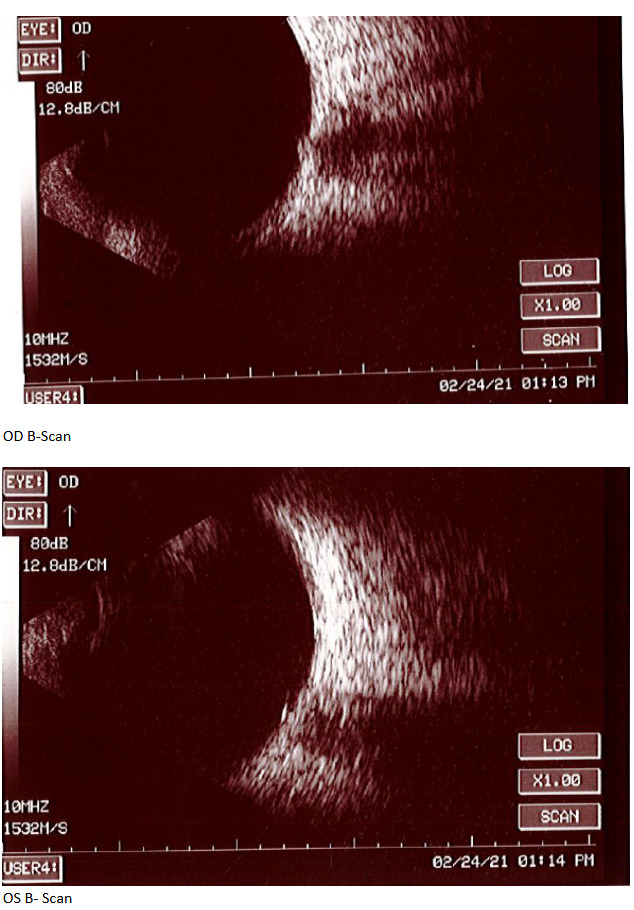

At the end of this visit, a diagnosis of optic nerve head drusen was determined due to the findings on the B-Scan. A highly reflective foci was seen due to the calcification present on the optic nerve head. There was no hyperflourescence seen on the fundus autoflourescent photos, but the drusen were likely buried. A 3-month follow-up was scheduled for repeat dilated fundus exam to ensure hemorrhages were resolving and no changes to the optic nerve head or visual acuity were occurring. The patient was educated on the condition of optic nerve head drusen and its effects on visual fields and vision. He was educated to return to clinic immediately if any changes were noted before the follow-up in 3 months.

B-Scan will show the calcification as a highly reflective foci over the optic nerve using low gain. B-scan imaging has been found a superior test over FAF and computed tomography (CT) to differentiate ONHD and disc edema. It is easy to use, inexpensive, and can even be performed on children. Ultrasonography is dependent upon the calcium content of the drusen. Therefore, some studies have shown that less than 50% of cases of disc drusen are found by ultrasound.7 This is similar with CT scans as well. CT will amplify the drusen in its images if the calcification content is great enough, but is not a method of choice to solely determine optic disc drusen due to high cost, radiation exposure to the patient, and furthermore, any slices greater that 1.5 mm can easily miss disc drusen.7 Overall, B-scan is an excellent test to perform quickly in the determination of disc edema versus optic nerve head drusen, but in some cases drusen could be missed so this may not be the sole test in some cases. For years, B-scan has been considered the gold standard for the diagnosis of ODD, but with the addition of EDI-OCT, physicians may find themselves relying more heavily on newer technology. B-scans do not provide us with clear information about the structural integrity of the neural retina as the OCT does.